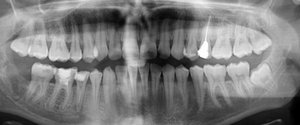

Данный зуб однозначно подлежит удалению, главная причина, недостаток места и как следствие колоссальная скученность зубов.